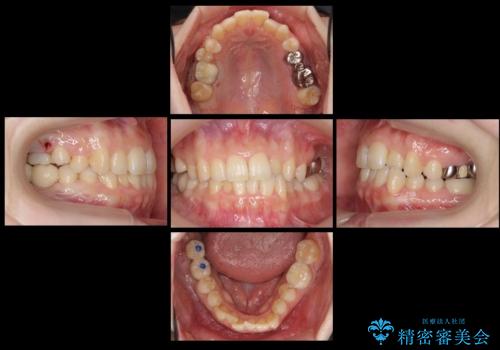

右上に部分矯正を行い、クリアランスを確保した後、右下にイプラントを2本埋入しています。

上の歯が伸びだしてきていたため、部分矯正を行い歯を移動させてから、向かい合わせの歯にインプラント治療を行っています。